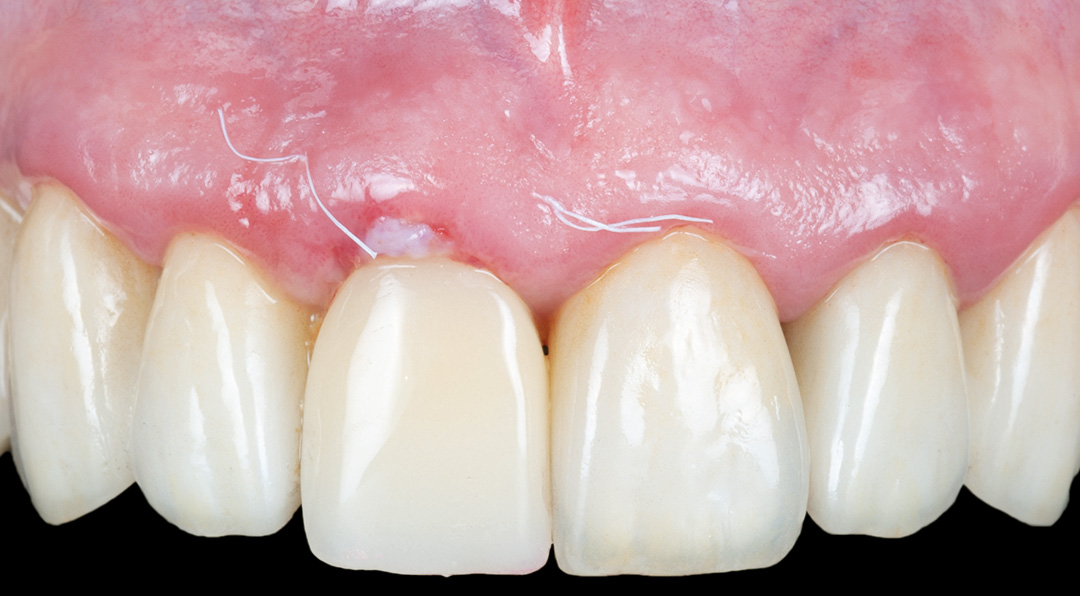

Four months post-placement, the implant site exhibited stable soft tissue contours and full graft integration. A screw-retained lithium disilicate crown was delivered and bonded to a customised anodised titanium abutment. Radiographs confirmed excellent osseointegration and bone preservation. Post-operative care included chlorhexidine 0.12% gel application twice daily for 14 days. The patient expressed high satisfaction with the aesthetic result, and no recession or tissue shrinkage was observed during the healing period.

A scanbody was used to register the implant position and a provisional restoration was designed in exocad software and milled in PMMA. The temporary restoration would be used to help stabilise the connective tissue graft, while also shaping the soft tissues to develop a good emergence profile. This is an important transition stage before the final restoration.

Main clinical outcomes

Surgical healing was uneventful and the patient reported no pain or discomfort. Papillae remained healthy and filled the embrasures completely. A final zirconia restoration was ultimately placed, designed to slightly alter the over-contoured emergence profile from the exocad software. This simplified the fitting protocol and further prevented the collapse of the hard or soft tissue during the final healing phase.